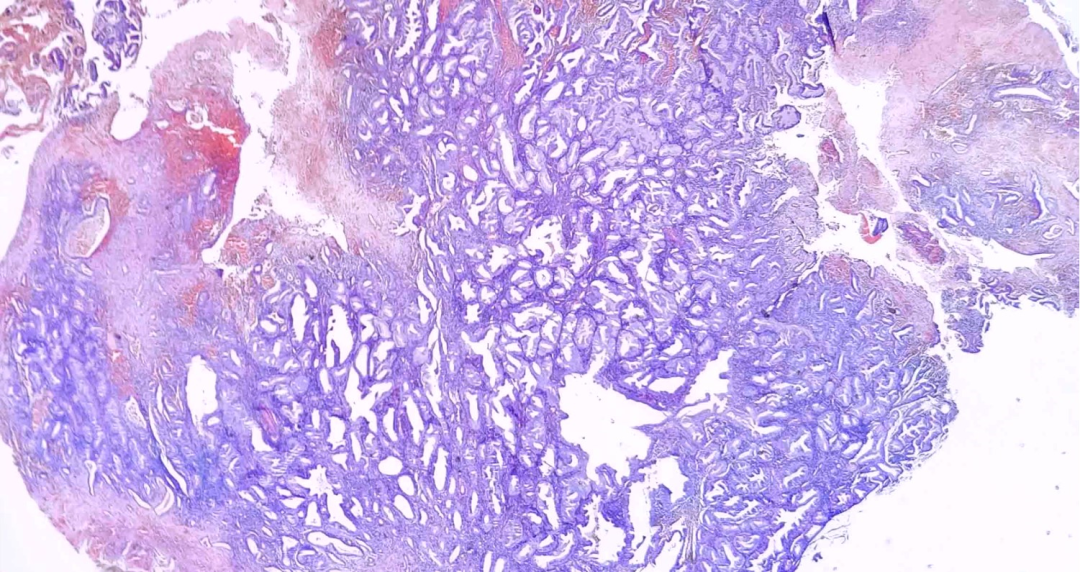

·子宫内膜息肉

纤维轴心含有大的厚壁血管的息肉样结构,胶原纤维为主的间质,可见囊性扩张及有时密集排列的腺体,内衬静止的萎缩性至微弱增生性子宫内膜上皮,低倍镜下呈息肉样,3个侧面衬覆上皮

表面上皮:通常变薄,呈萎缩或增生形态,偶尔呈乳头状增生,或脱落、出血 内部腺体:腺体形态不规则 (管状、分支或囊状扩张,与背景内膜腺体不同步),腺体长轴常与息肉表面平行,腺体功能通常不活跃 (少数为功能性),可伴化生性改变(纤毛化生、嗜酸性化生、粘液化生和鳞状化生) 内部间质:间质细胞多少不等,或呈纤维胶原样,常见多少不等厚壁血管,呈簇状聚集,有时可见退变的奇异核细胞、含铁血黄素沉积 伴随形态:1.息肉扭转: 常导致出血性脑梗死、上皮化生和反应性异型性;2.少见情况:间质平滑肌成分突出时,类似腺肌瘤 (腺肌瘤性息肉)

服用激素的患者,息肉可能出现乳头状增生;他莫昔芬治疗的患者,腺体常呈鹿角状,腺体周围有间质袖套(无异型及核分裂)